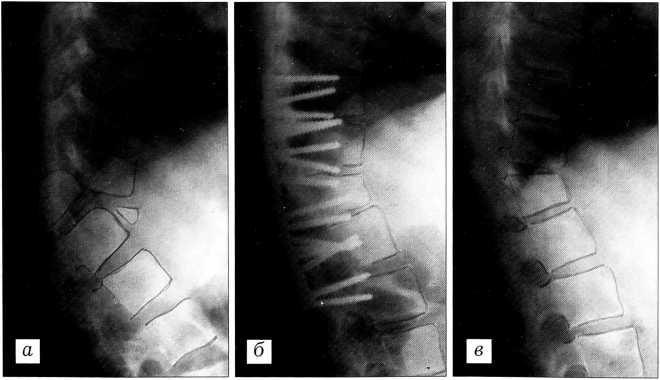

Больная Б.,12 лет, поступила с застарелым переломовывихом Т11_12 позвонков и прогрессирующей кифотической деформацией под углом 126°. Давность травмы 1 год. Ранее была неоднократно оперирована. 02.04.91 произведены укорачивающая вертебрэктомия Т12, вертебротомия T11-L1 позвонков, менингомиелорадикулолиз, пластика твердой мозговой оболочки, фиксация металлическими пластинами типа АО и винтами. Достигнута коррекция деформации позвоночника до угла 163° (68,5% от исходной) с улучшением симметрии ростковых зон позвонков. После удаления металлофиксатора деформации позвоночника не последовало (рис. 3).

Рис. 3. Спондилограммы больной Б. до операции (а), после операции (б) и после удаления фиксатора (в).